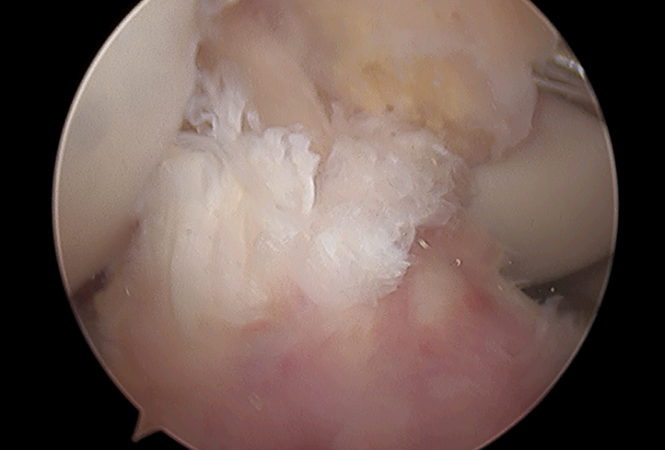

수술전

수술후

미세천공술 전

미세천공술 후